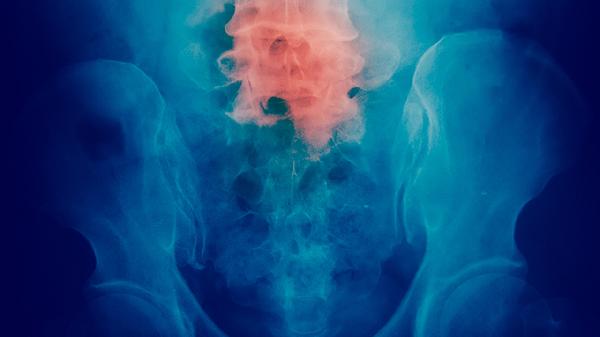

贝伐珠单抗注射液通过阻断血管内皮生长因子抑制肿瘤血管生成,适用于转移性结直肠癌和非小细胞肺癌等。可能引起高血压和蛋白尿等不良反应,严重出血或胃肠穿孔患者禁用。需在化疗基础上联合使用。